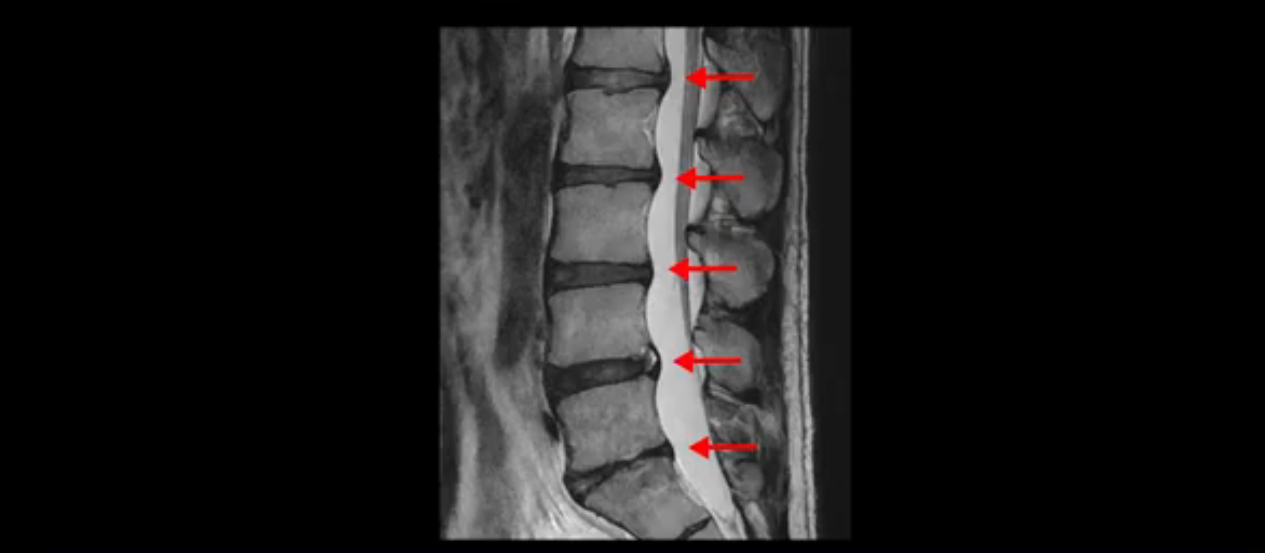

우선 이분 MRI를 보면 허리 모든 마디의 디스크가 퇴행되어 있고

여러 마디의 디스크가 조금씩 밀려나와 보이고, 디스크 섬유륜도 찢어져 보이는 마디도 보입니다.

그런데 이분의 증상과 MRI가 전혀 일치하지 않는데, 왜 그런지 지금부터 자세히 설명드립니다. 이분 증상은 앉으면 엉치와 허리가 심하게 아파 10분 이상 앉는 게 어렵고 양쪽 발가락이 앉아있을 때나 누워있을 때 다 저립니다. 걸을 때도 아파서 10분 걷기도 어렵습니다. MRI를 마디마디 살펴보면 1번 2번은 오른쪽으로 살짝 밀려나온 디스크가 있지만 전혀 심하지 않고, 뒤에 또 설명하겠지만 최근에 밀려나온 급성 디스크가 아니고 오래된 디스크로 판단됩니다.

2번 3번도 비교적 디스크 상태는 좋고 신경 구멍 넓이도 아주 넓습니다.

3번 4번도 마찬가지로 디스크상태 좋아 보이고 신경 눌림 전혀 없어 보입니다.

4번 5번은 가운데로 섬유륜이 찢어져서 디스크가 살짝 밀려나와 있지만 역시나 최근에 찢어지고 밀려나온 걸로 판단되지 않고 오래 전에 찢어진 흔적으로 보입니다.

왜 최근에 찢어진 급성이 아니고 오래된 거라고 하는지 이 부분도 뒤에 한꺼번에 설명 드리겠습니다.

5번 1번 역시 가운데로 디스크 조금 밀려 나와있지만 신경 공간 넓이는 아주 넓어서 신경 눌림 있을 거라고 예상이 안됩니다.